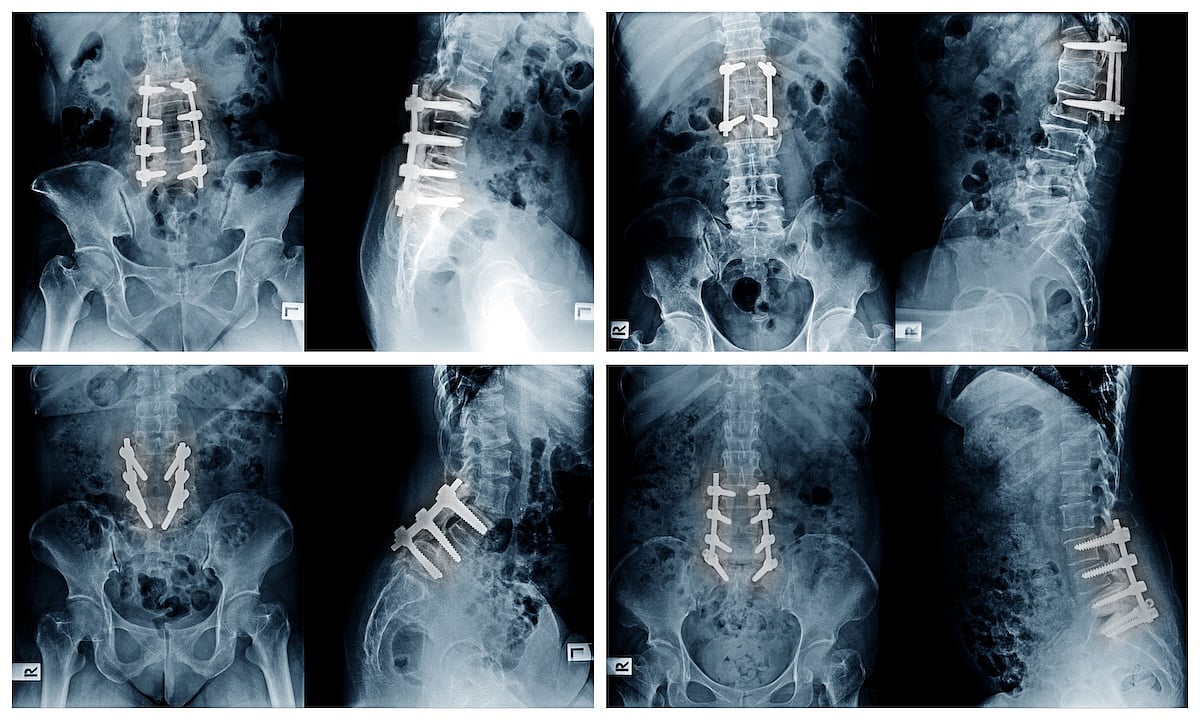

FRIDAY, Oct. 17, 2025 (HealthDay News) — The placement of orthopedic screws and rods during spinal fusion surgery should vary depending on whether you’re a man or a woman, according to a new study.

Sex-based anatomical differences in the pelvis make it essential that surgeons approach men and women differently when fusing and stabilizing the spine, researchers recently wrote in the journal Spine Deformity.

Men have a narrower pelvis, which means that screws and rods need to be placed differently for them than in women.

Specifically, it’s harder to connect screws to rods in a straight line in men, leading to additional rod bending or other adjustments during surgery, researchers said.

Surgery for low back pain sometimes requires that the lower spine be fused, with rods and screws attaching the vertebrae of the lower spine to the pelvis, according to the University of Maryland Medical Center.

For the study, researchers compared 185 cases performed by three orthopedic surgeons, using X-rays and CT scans to assess screw placement and anatomical differences between male and female patients.

Results showed that the narrower pelvis in men causes rods to angle inward, rather than the parallel alignment that’s preferred.